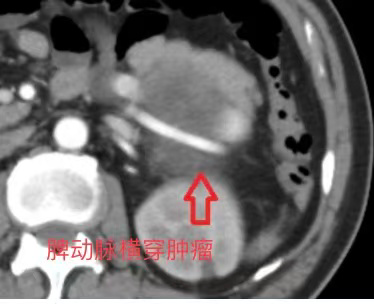

患者病情初步稳定后,查明出血根源成为彻底治愈的关键。进一步检查证实,此次险情的“元凶”是一枚直径约15cm的胃巨大肿瘤——该肿瘤包绕脾脏血管、压迫胰腺,如何在手术中保留脾脏和胰腺是一大难题,手术难度系数极高。